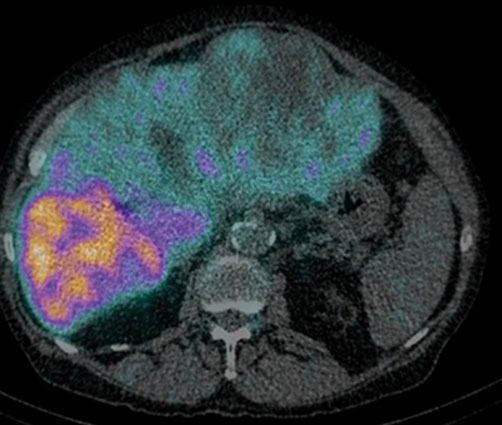

TARE, also known as Yttrium-90 (Y-90) Radioembolization, is an advanced form of internal radiation therapy for liver tumors.

Tiny radioactive beads (microspheres) are delivered into liver arteries

Radiation targets the tumor from inside

Minimal radiation exposure to healthy liver tissue

Benefits of TARE:

Highly precise treatment

Suitable for advanced or inoperable liver tumors

Fewer side effects compared to external radiation

Can be used when TACE is not effective